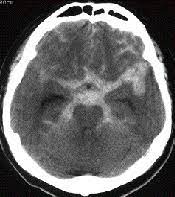

くも膜下出血のctç

くも膜下出血のctç"»åƒã¨è§£å‰– つねぴーblog 内ç§'å°‚æ"»åŒ» from cdn-ak.f.st-hatena.com